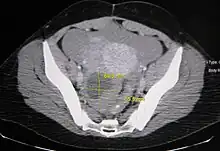

An Axial CT demonstrating a large hemorrhagic ovarian cyst. The cyst is delineated by the yellow bars with blood seen anteriorly.